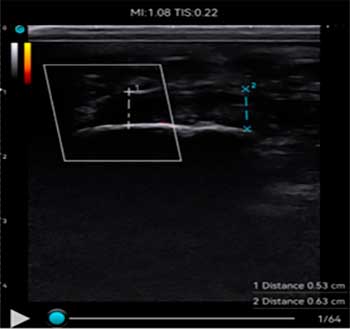

La utilización de un ecógrafo para diagnosticar la fasciosis plantar es esencial y es la herramienta más idónea para su examen.

En ecografía observamos una señal hipoecoica con separación de las fibras de la fascia plantar. El valor normal de fascia plantar sana es de 3mm. Es importante realizar un estudio ecográfico comparativo en el otro pie para visualizar el rango de grosor de la otra fascia.

A continuación adjunto varios casos de imágenes ecográficas con fasciopatía plantar: